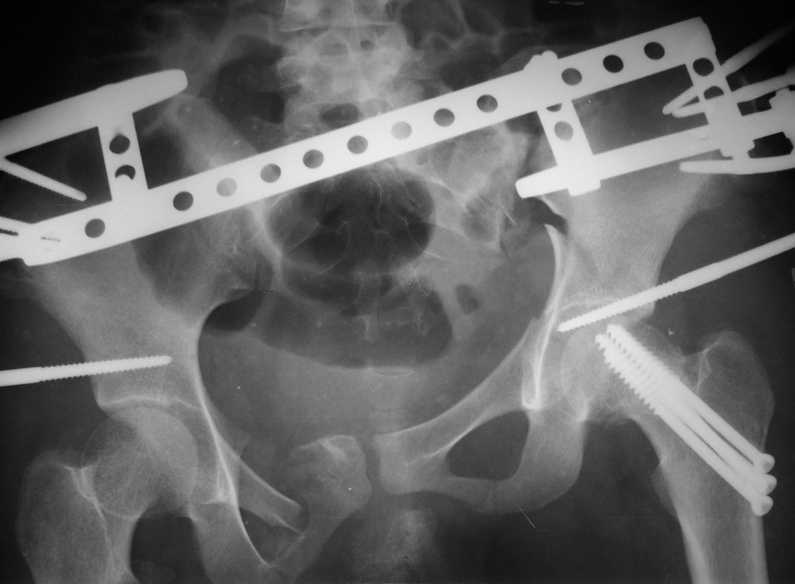

Больная К., 18 лет. Падение с высоты 5 этажа в январе 2008 г.

Остеосинтез винтами перелома шейки бедра слева и оскольчатого перелома

костей таза аппаратом внешней фиксации. Демонтаж аппарата через 3

мес., нагрузка на левую ногу через 6 мес. Через год стала ходить без

палочки. С марта 2009 года стала замечать укорочение левой нижней

конечности, появились боли в левом тазобедренном суставе. В настоящее

время укорочение 8 см., выраженная приводящая контрактура в левом

тазобедренном суставе. На обсуждение выносится тактика: сначала

удлинить конечность, а затем выполнить эндопротезирование или сразу

произвести эндопротезирование.

The patient with posttraumatic AVN of femoral head and fracture of the

pelvis. The trauma was 1,5 year ago. Now she has the pain in the hip

and the shortening 8 cm